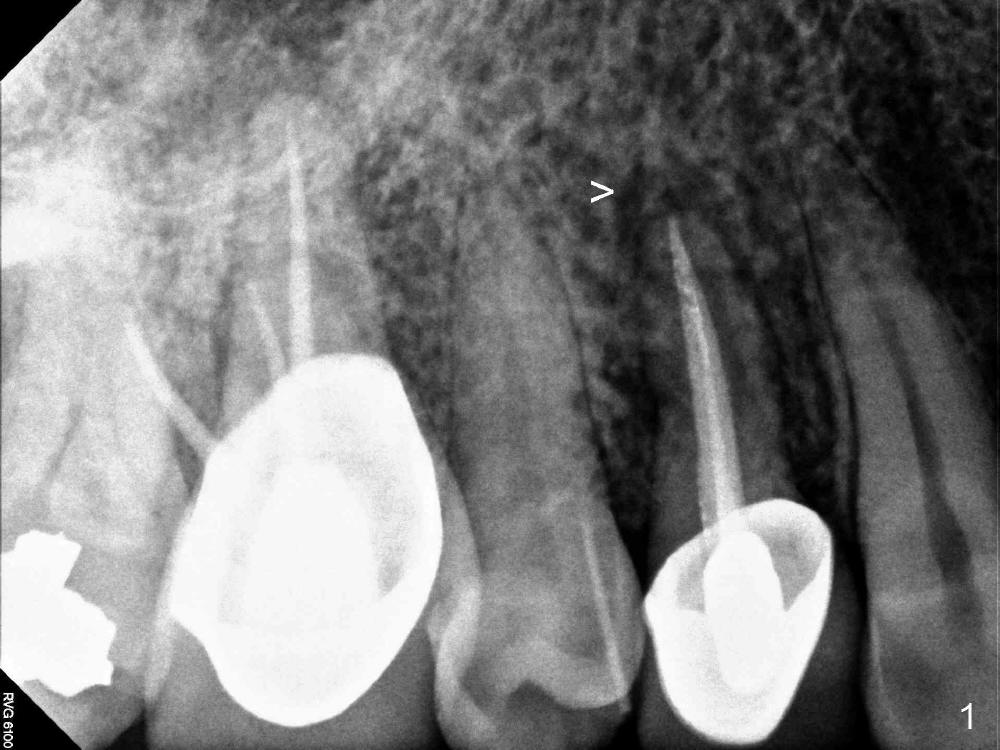

A 60-year-old man has had a fistula for several months (Fig.1,2). Plan A is to place a SM implant (4.5x14 mm, Fig.3), cemented abutment and immediate provisional. After atraumatic extraction, a 2 mm pilot drill is used to create osteotomy at the depth of 14 mm, followed by 2.5 and 3.0 mm reamers at the same depth and insertion of 4.5 mm tap drill with slow handpiece to determine whether there is enough stability. If yes, place the implant mentioned above. If not, use a longer implant. Do you have a 18 mm bone-level implant (UF)? If not, I will bring a 4.5x20 mm gingiva-level tapered or straight implant.